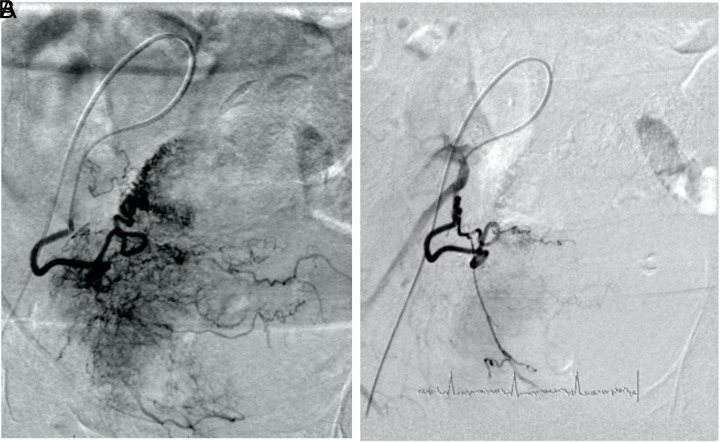

Methods: Twelve male patients with intractable hematuria due to bladder carcinoma were included in the study. A total of 17 selective transarterial embolization procedures (bilateral in 5 patients) were performed in 12 patients with microspherical particles and microcoils.

Results: Complete control of bleeding was achieved in 9 patients after the procedures whereas the need for transfusion continued in 3 patients. Approximately 75% bleeding control was achieved during our average 6-month (4- to 12-month) follow-up period. After the procedure, the patients had mild complaints that lasted for a few days, such as pain (66%), fever (42%), and nausea (50%). No major complications occurred.

Conclusion: Selective transarterial internal iliac artery embolization is a reliable method that can be used for the palliative treatment of intractable hematuria due to bladder carcinomas.